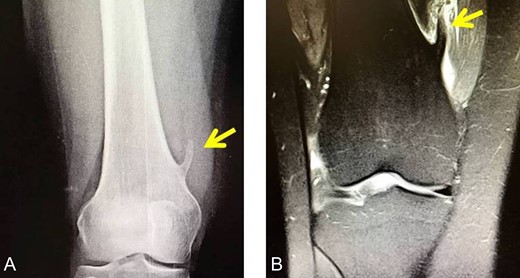

X-rays revealed an extra-articular mass at the medial aspect of the distal femur (Fig. 1A). Magnetic resonance imaging (MRI) confirmed the radiograph findings and no meniscal and ligament rupture or chondral defects were revealed. These characteristics were consistent with osteochondroma (Fig. 1B). Under general anesthesia, a standard antero-lateral portal used to access arthroscopically the knee. Cartilage surface, cruciate ligaments and menisci were normal. The osteochondroma was located extra-articularly, at the medial supracondylar side of the distal femur. Through a supero-medial portal and by perforating the capsule and a part of a medialis vastus muscle, the extra-articular lesion was reached arthroscopically (Fig. 2A). With an osteotome, the lesion was resected and removed with a grasper through the supero-medial portal (Fig. 2B). The remaining bony surface was abraded by a motorized shaver (Fig. 2C). The exostosis had maximum dimensions 3.1 × 2.5 cm. Histopathological examination confirmed the osteochondroma diagnosis.

(A) The X-ray depicting the exostosis (yellow arrow), (B) MRI depiction of the exostosis.